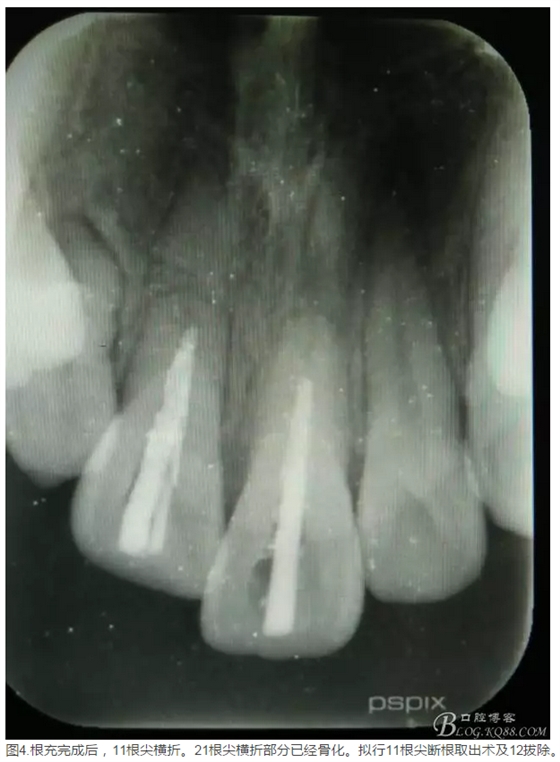

患者、李xx、男、15歲,主訴:牙不齊,矯正牙齒。??茩z查:發(fā)現(xiàn)11、21根尖三分之一折斷,患者否認有外傷史。正畸科治療建議如圖1.。術前簽手術同意書。